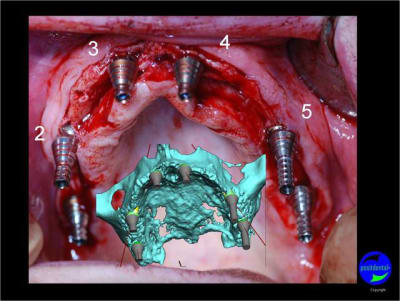

Expansion, condensation guidée

gros travail pour mettre au point un guide pour expansion et belle maitrise chirurgicale !!!

Il est certain que tu as bien évolué sur le positionnement mécanique et la répartition des implants.

J'aurais aimé 2 implants de plus, car dans ton cas, 1 implant perdu et ça va etre difficile à gérer.

De plus comme je te l'ai déjà dis, je ne suis pas pour la MCI en expansion, mais il est évident que je ne sais pas tout et que tu fais un gros travail.

La 23 donne un peu un effet dracula, mais super boulot du chir et concepteur du guide.

C'est la première fois que je vois un cas avec expansion.

votre avis sur ce cas clinique

Le guide chirurgical, positionneur d’implants reste en place jusqu’à la pose des implants.